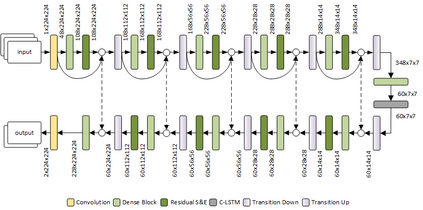

COVID-19 infection caused by SARS-CoV-2 pathogen is a catastrophic pandemic outbreak all over the world with exponential increasing of confirmed cases and, unfortunately, deaths. In this work we propose an AI-powered pipeline, based on the deep-learning paradigm, for automated COVID-19 detection and lesion categorization from CT scans. We first propose a new segmentation module aimed at identifying automatically lung parenchyma and lobes. Next, we combined such segmentation network with classification networks for COVID-19 identification and lesion categorization. We compare the obtained classification results with those obtained by three expert radiologists on a dataset consisting of 162 CT scans. Results showed a sensitivity of 90\% and a specificity of 93.5% for COVID-19 detection, outperforming those yielded by the expert radiologists, and an average lesion categorization accuracy of over 84%. Results also show that a significant role is played by prior lung and lobe segmentation that allowed us to enhance performance by over 20 percent points. The interpretation of the trained AI models, moreover, reveals that the most significant areas for supporting the decision on COVID-19 identification are consistent with the lesions clinically associated to the virus, i.e., crazy paving, consolidation and ground glass. This means that the artificial models are able to discriminate a positive patient from a negative one (both controls and patients with interstitial pneumonia tested negative to COVID) by evaluating the presence of those lesions into CT scans. Finally, the AI models are integrated into a user-friendly GUI to support AI explainability for radiologists, which is publicly available at http://perceivelab.com/covid-ai.